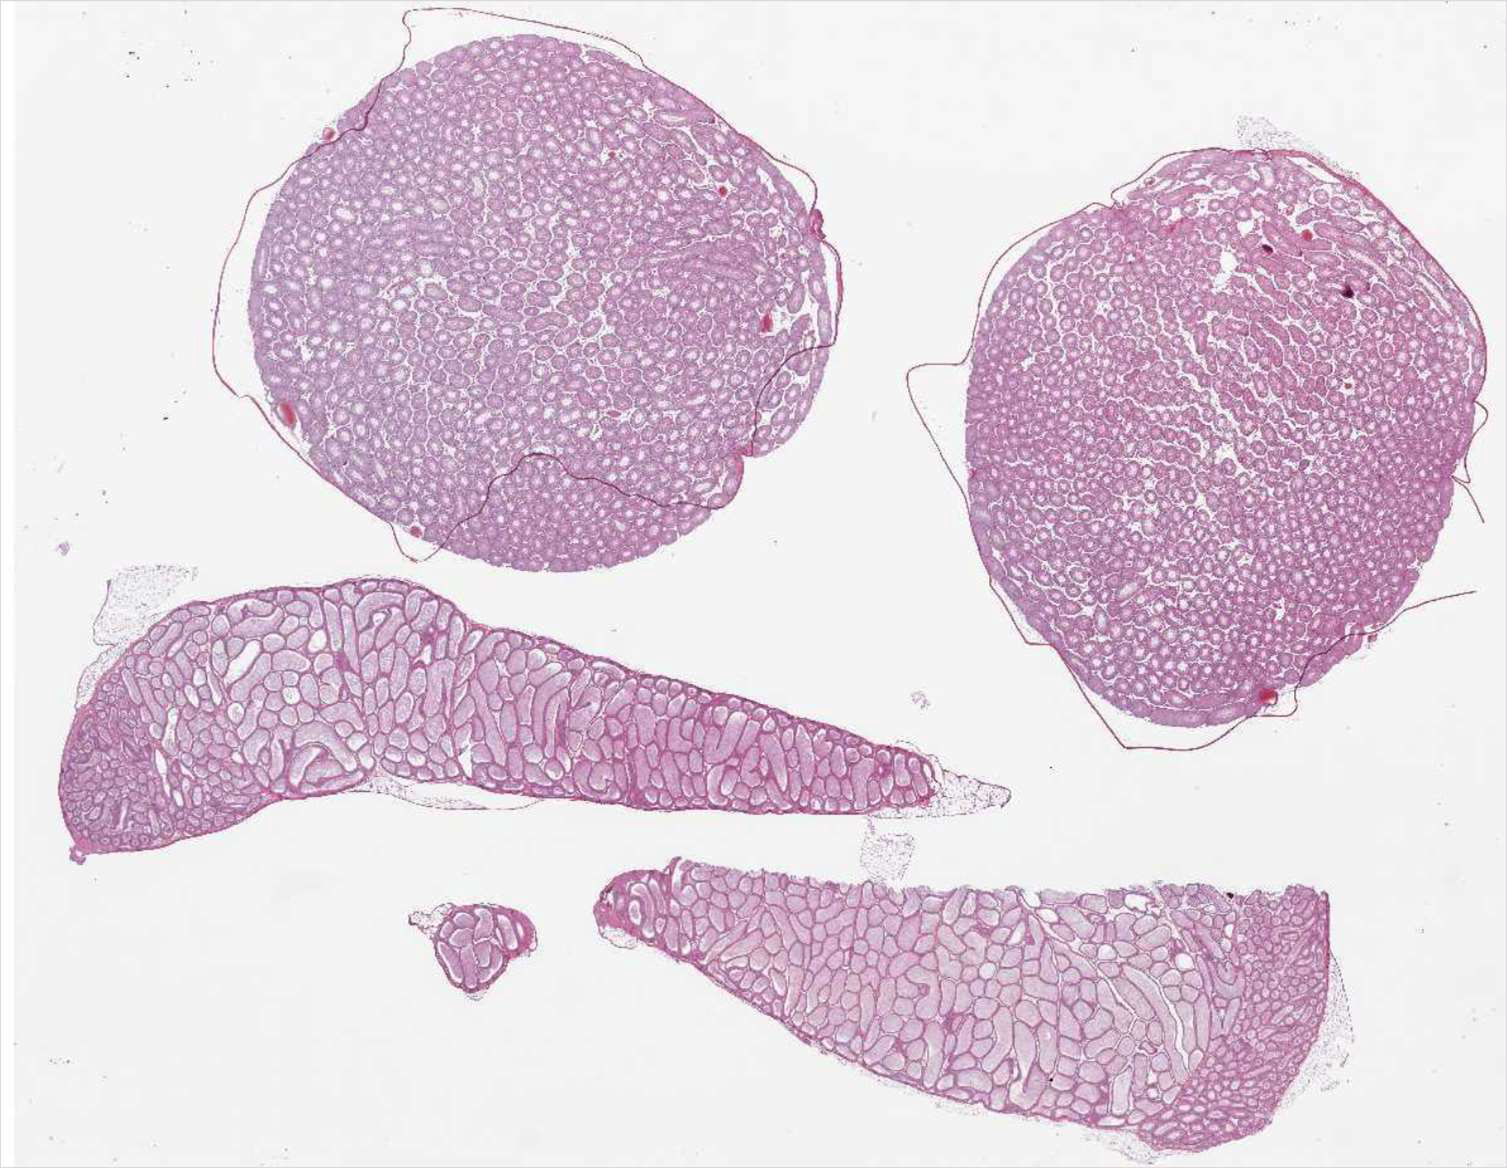

Testes

Testes and epididymides

Testis

1

2

3

4

5

61. Tunica/capsule,

2. Tubuli,

3. Sertoli cell,

4. Spermatide,

5. Spermatogonium,

6. Leydig cellUterus